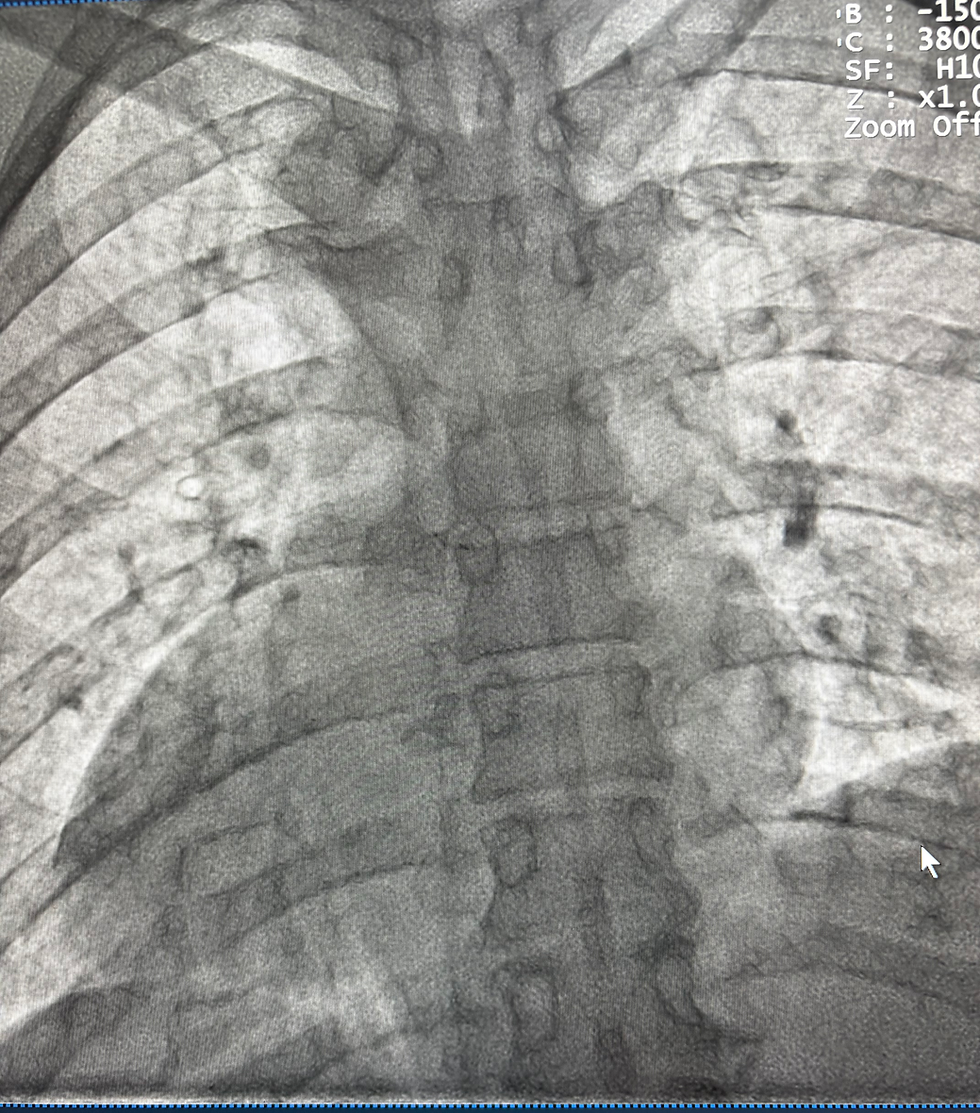

A angioplastia coronária é um procedimento que devolve o fluxo de sangue às artérias do coração, melhorando sintomas como dor no peito e falta de ar. Mas o sucesso da angioplastia não termina na sala de hemodinâmica: o acompanhamento médico e os cuidados após o procedimento são fundamentais para garantir uma boa recuperação e evitar novas complicações.